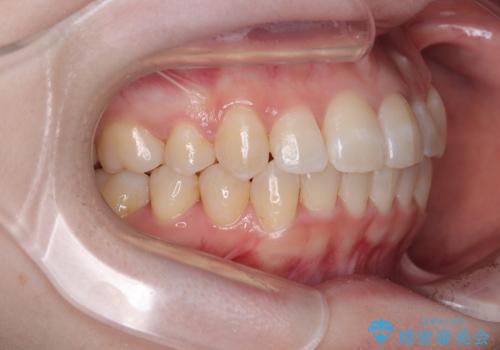

補助装置を併用したおかげで、出っ歯になることなくスムーズに治療を終えることができました。